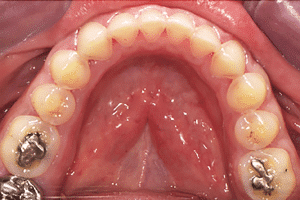

Lors de cette première consultation, en plus de l’examen clinique, on réalise une empreinte optique (Fig.2).

Fig.2.

Elle a deux buts. Le premier relève de la communication : il est plus facile pour la patiente de se rendre compte de l’état d’usure de ses dents avec une image 3D en plus des photographies et du miroir de courtoisie. Le deuxième but est l’analyse de l’occlusion. Grâce au logiciel d’exploitation (ici, Dexis IS Scan Flow), on se rend bien compte que l’occlusion est serrée avec des contacts extrêmement forts à droite (en rouge sur le Scan Flow). Il est alors facile de conclure et d’expliquer dès à présent à la patiente qu’il est impossible de restaurer son sourire dans cette situation occlusale. Pour redonner de la hauteur aux dents antérieures il faut de la place, créée soit par soustraction en préparant les dents antérieures, soit par addition en relevant la hauteur des dents postérieures. La patiente fait rapidement son choix. Pour nous, cela signifie qu’il va falloir augmenter la DVO.